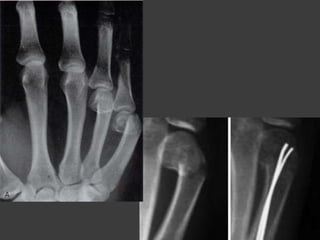

Fractura de 1er

Metacarpiano

Clasificacion de MacNeal

Fractura de Bennett

Cuadro Clinico

Tratamiento

 Reduccion mediante

traccion y compresion

 Traccion continua con

esparadrapo (

abduccion y extension

por 3 a 4 sem ) y yeso

 Fijacion con agujas de

Kirschner al trapecio o

2do metacarpiano